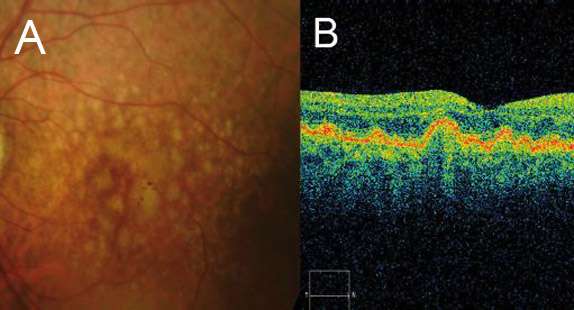

EARLY AMD

INTERMEDIATE AMD

LATE AMD